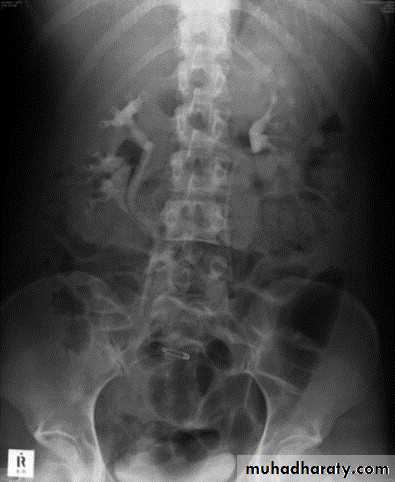

IVU :

- There is rounded or elliptical dilatation of lower end of ureter with thin lineal filling defect around it , resembling (cobra head appearance),

- Proximal dilatation of rest of ureter .

- In advanced cases hydronephrosis .

- In obstructed ureterocele , filling defect in the bladder